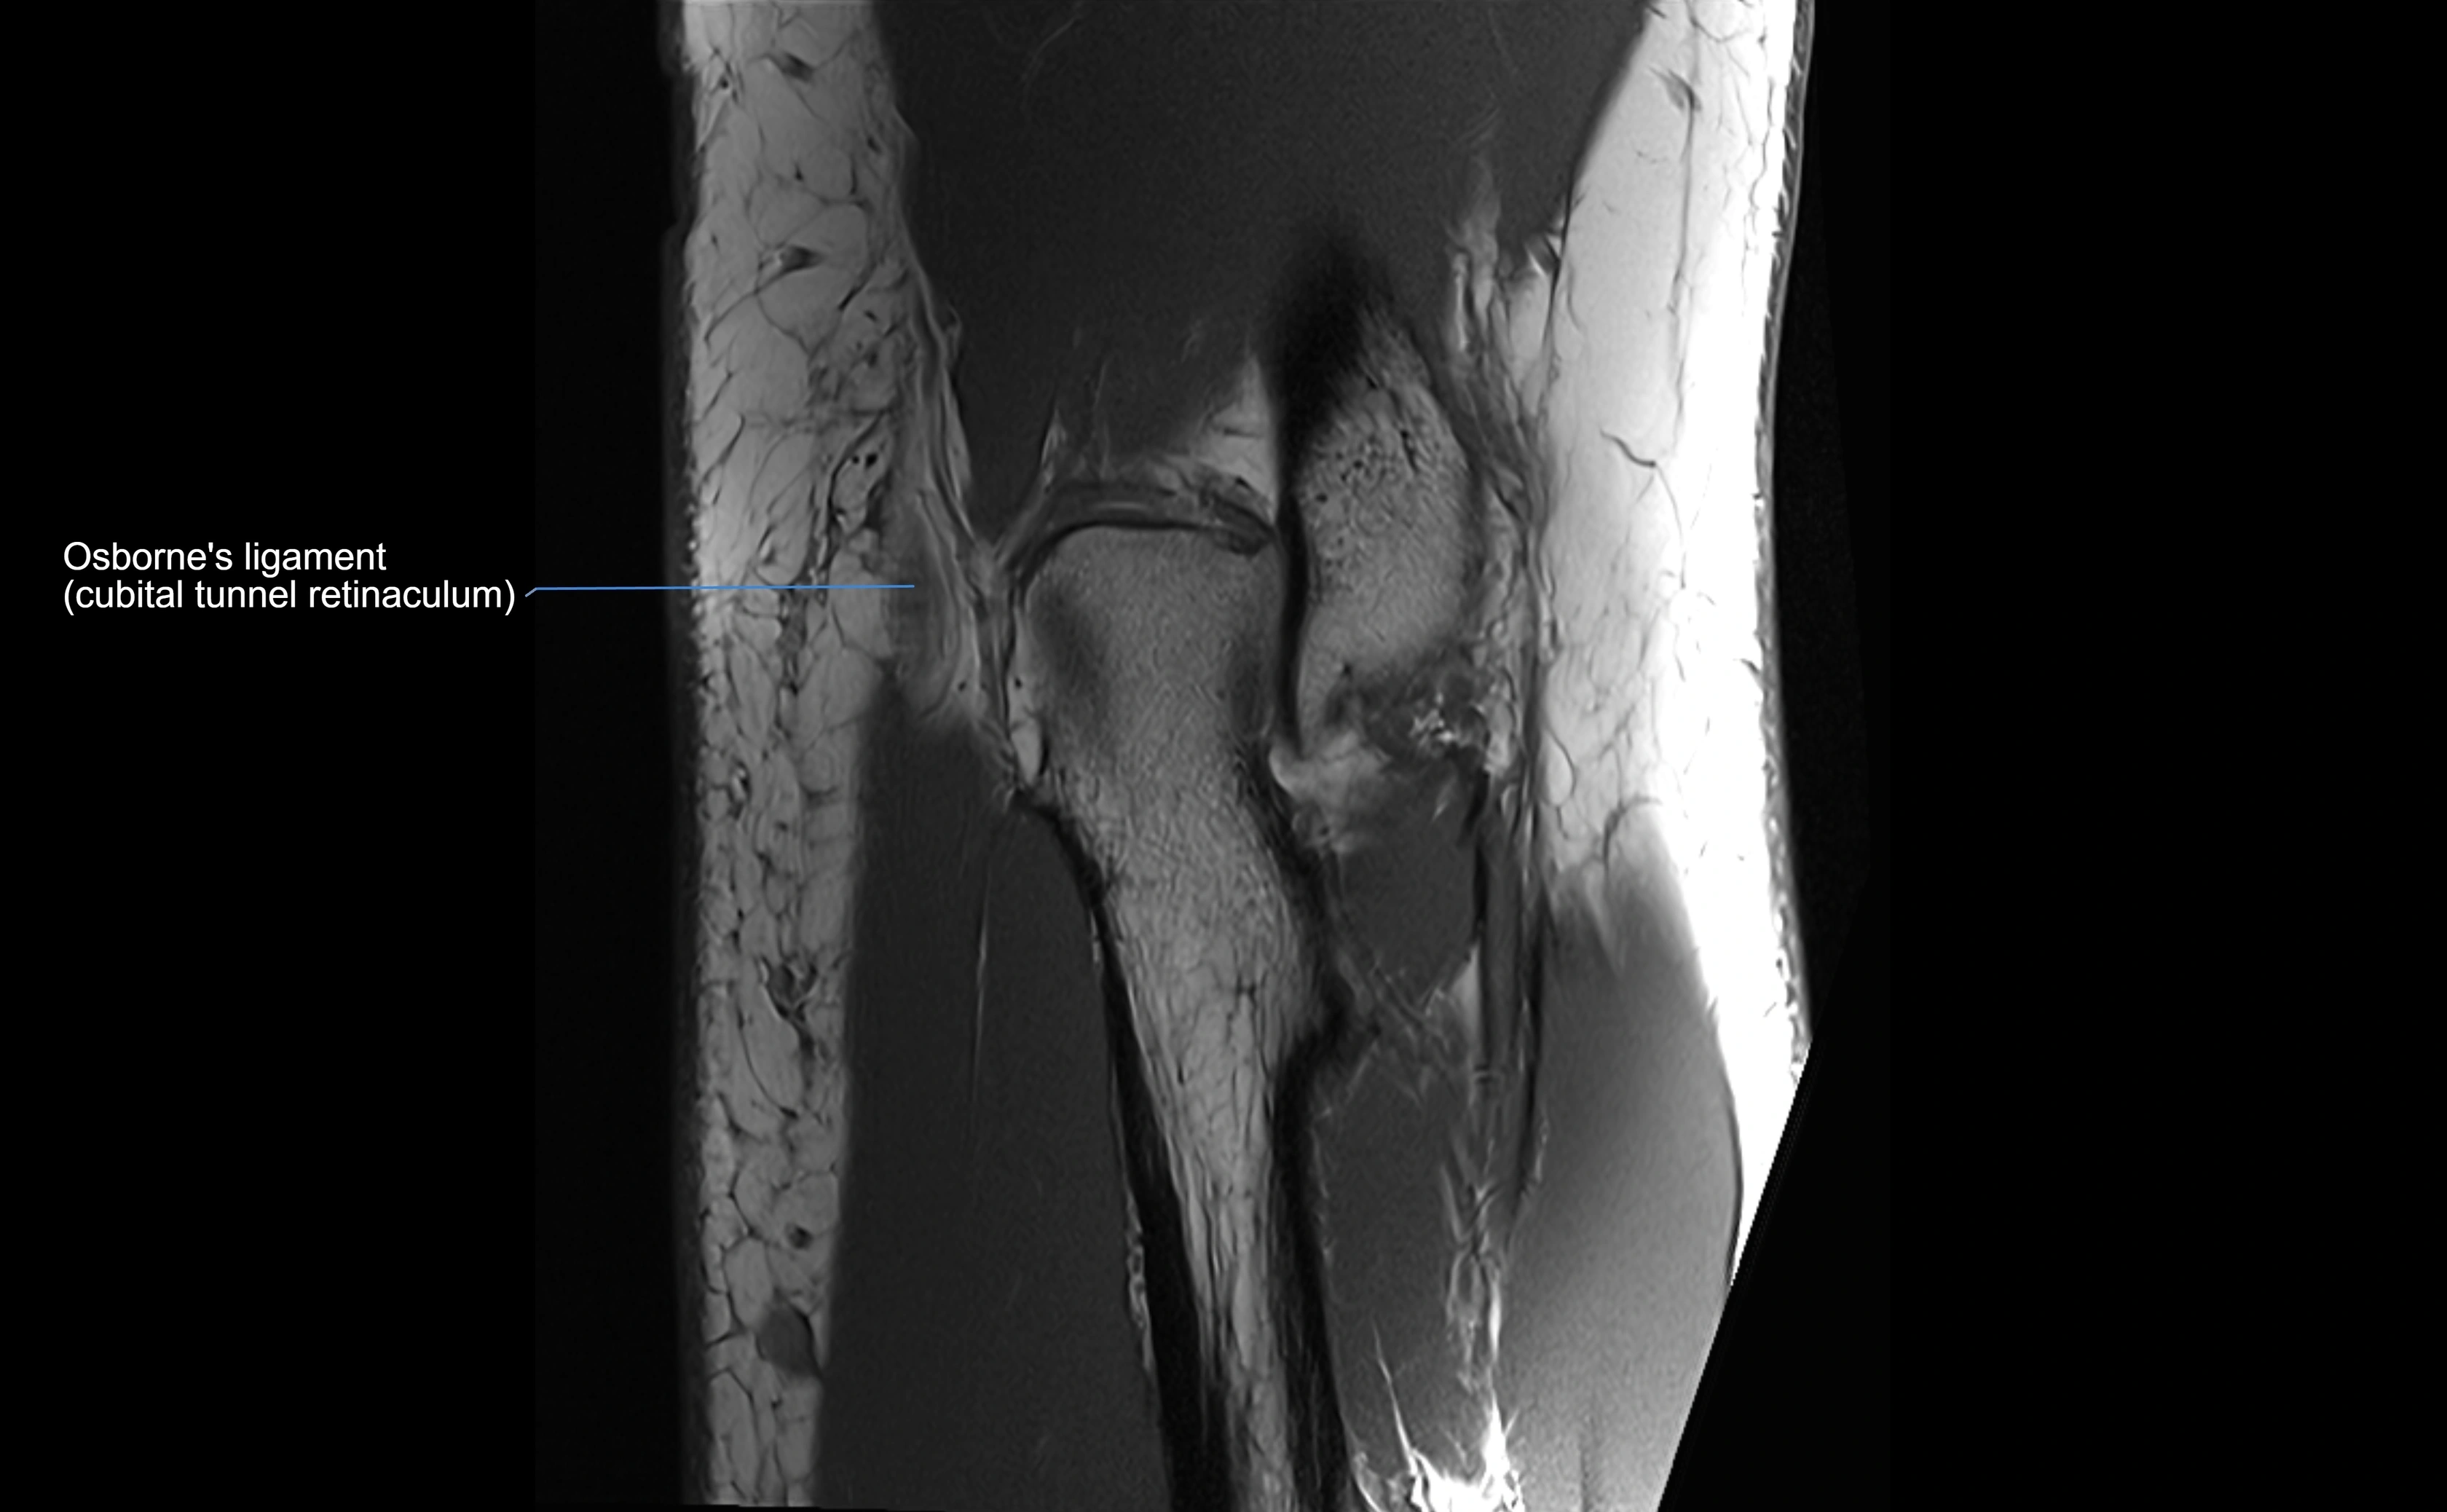

MRI Appearance

T1-weighted images:

• Ligament: low signal intensity (dark), appearing as a continuous band around the radial head.

• Adjacent fat and marrow: bright, creating contrast with the ligament.

• Thickening or disruption indicates injury or fibrosis.

• Joint capsule and synovium seen as thin low-signal lines contiguous with ligament margins.

T2-weighted images:

• Ligament: low signal (dark) with clear delineation from joint fluid.

• Fluid or edema: bright hyperintense, separating or surrounding the ligament in partial tears.

• Complete tear: discontinuity or non-visualization of ligament fibers, often with joint effusion.

STIR:

• Normal ligament: dark band encircling radial head.

• Pathology: bright hyperintense periligamentous signal suggesting edema, sprain, or partial tear.